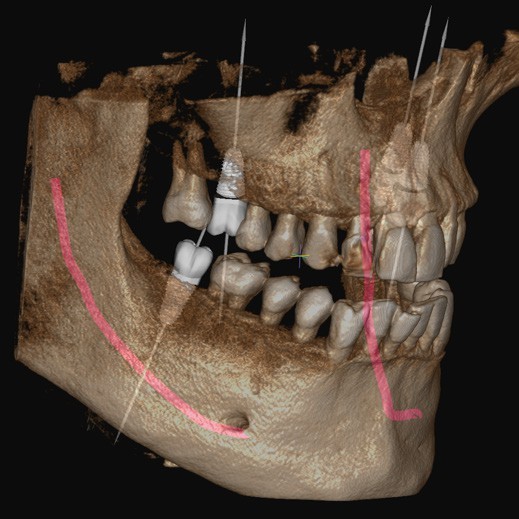

Planificarea implantului asistată de Inteligență Artificială (AI)

Rainbow™ CT integrează funcții avansate de Inteligență Artificială pentru a automatiza și simplifica sarcinile de rutină. De la identificarea poziției dinților lipsă până la stabilirea poziției inițiale a implantului și coroanei, AI-ul Dentium asigură o planificare eficientă și precisă a tratamentelor.

Implant/Coroană: Inteligența Artificială Dentium detectează automat poziția dinților lipsă și stabilește poziția inițială a implantului și coroanei pentru a simplifica planificarea implantului.

Nerv: Identificarea canalului nervului alveolar inferior se face în doar 15 secunde. Inteligența Artificială Dentium asigură un diagnostic mai precis și de încredere.

Arcada: Algoritmul AI generează automat linia arcadei în doar câteva secunde, cu o precizie ridicată.